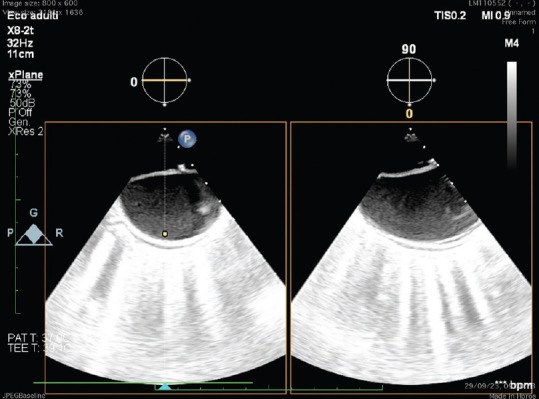

胸腔内血管主动脉修复术(TEVAR)在治疗急性和慢性主动脉病变方面发挥着核心作用。随着经导管结构性心脏手术的发展,超声心动图已成为手术指导的关键。尽管超声心动图在心脏介入手术中的应用已达成共识,但在主动脉手术中的超声辅助并没有广泛标准化。一名 71 岁的肥胖男子患有慢性 B 型主动脉夹层,在经食道超声引导下使用单支主动脉支架移植物(Endovastec™ Castor™)接受了 TEVAR 手术。术前评估确认降胸主动脉存在主动脉夹层,有一个后方真腔(TL)和一个前方假腔(FL),主动脉瓣解剖结构和功能正常,左心室功能正常,腔内无血栓,也没有妨碍支架移植物最佳植入的主动脉斑块。手术过程中,经食道超声心动图(TEE)监测导丝的定位、胸腔内支架导管的到达,然后将其植入主动脉弓和降主动脉。术后 TEE 评估强调支架移植物完全展开,无泄漏,并成功排除了开始形成血栓的 FL。血管造影证实动脉瘤已被排除,且无内漏。该临床病例展示了经食道超声心动图引导如何通过减少透视时间和造影剂的使用来改善 TEVAR 手术,并通过实时监测 TL 和 FL 来更好地评估夹层解剖结构。总之,经超声心动图可作为术中辅助成像工具,在术前、术中和术后提供良好的信息,提高 TEVAR 的成功率和安全性。

Thoracic endovascular aortic repair (TEVAR) plays a central role in managing acute and chronic aortic pathologies. With the advancement of transcatheter structural heart procedures, echocardiography has become a key in procedural guidance. Despite consensus on its use for cardiac interventions, ultrasound assistance in aortic procedures is not widely standardized. A 71-year-old obese man with chronic type B aortic dissection underwent a TEVAR procedure, using a single-branched aortic stent graft (Endovastec™ Castor™) and with transesophageal ultrasound guidance. The preprocedural assessment confirmed the presence of aortic dissection of the descending thoracic aorta with a posterior true lumen (TL) and an anterior false lumen (FL), normal aortic valve anatomy and function, normal left ventricular function, absence of intracavity thrombus, and absence of aortic plaques that could prevent the optimal implantation of the stent graft. During the procedure, a transesophageal echocardiogram (TEE) monitored the positioning of the guide wires, the arrival of the catheter of the thoracic endoprosthesis, and then the implantation of this at the level of the aortic arch and the descending thoracic aorta. Postprocedure TEE evaluation underlined full stent-graft deployment without leaks and successful exclusion of FL with the beginning of thrombosis. Angiography confirms the exclusion of the aneurysm and the absence of endoleaks. This clinical case demonstrates how transesophageal echocardiographic guidance can improve the TEVAR procedure by minimizing fluoroscopy time, contrast medium use, and enabling a better assessment of the dissection anatomy with real-time monitoring of both the TL and the FL. In conclusion, TEE can serve as an auxiliary intraoperative imaging tool to provide good information before, during, and after the procedure, increasing the success and safety of the TEVAR.